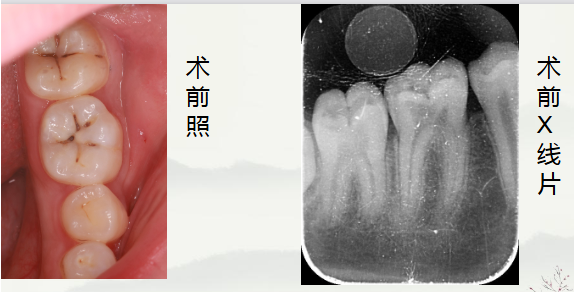

牙齿检查情况:左下第一磨牙见颌面坏,探针可探及洞,叩诊++,无松动,牙龈无明显红肿,冶热刺激敏感。

通过术前照与X线片,小牙片可见,颌面龋坏,远中邻面龋坏,叩+,松动-,

夜间自发痛,冷热刺激与对照牙对比反应明显。诊断为急性牙髓炎